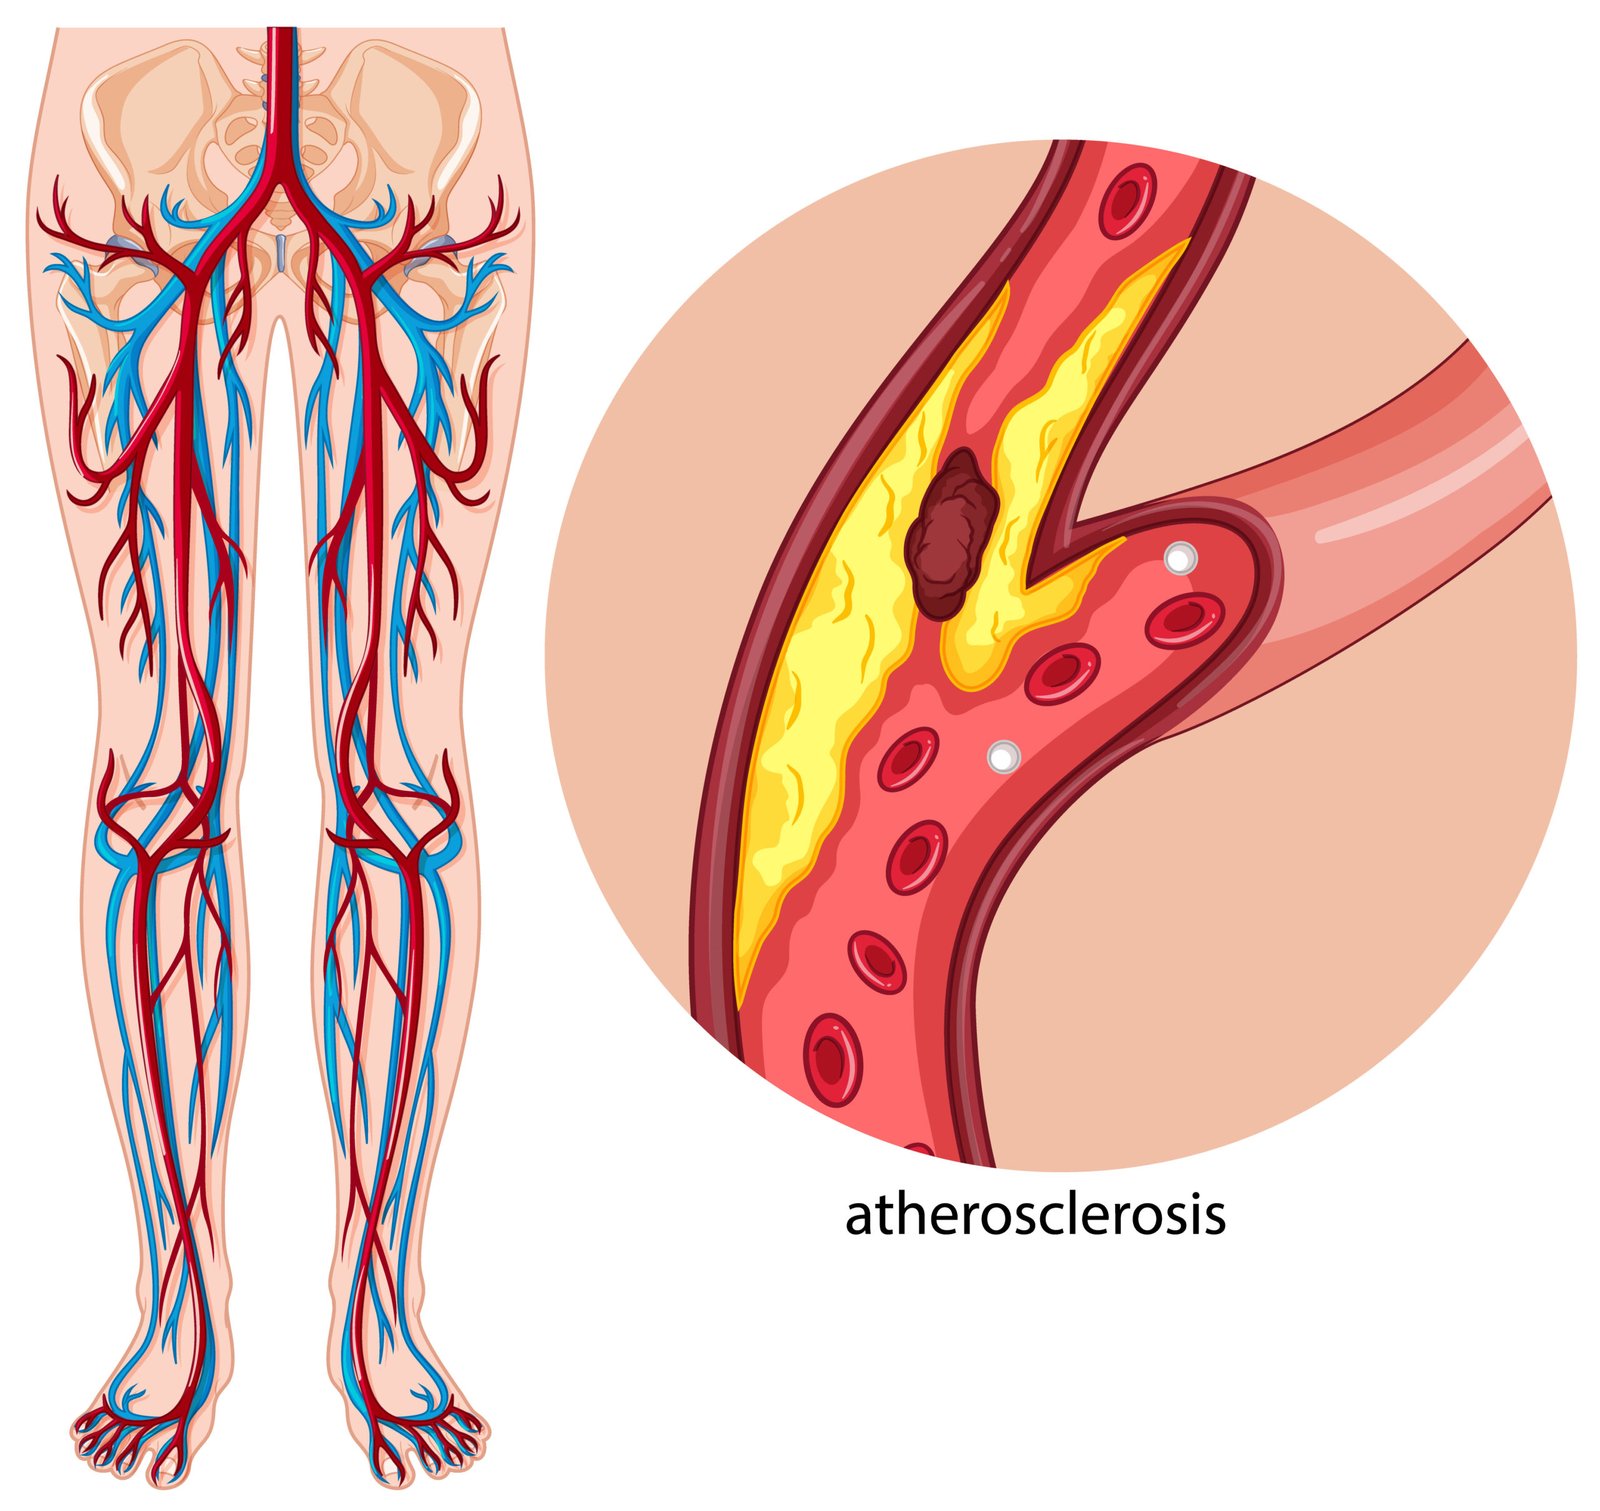

Vascular screenings are non-invasive medical tests used to assess the health of blood vessels and detect any abnormalities or blockages. These screenings are essential for identifying conditions such as:

- High blood pressure or cholesterol: Both of these conditions contribute to the build-up of plaque in the arteries, increasing the risk of blockages or narrowing.